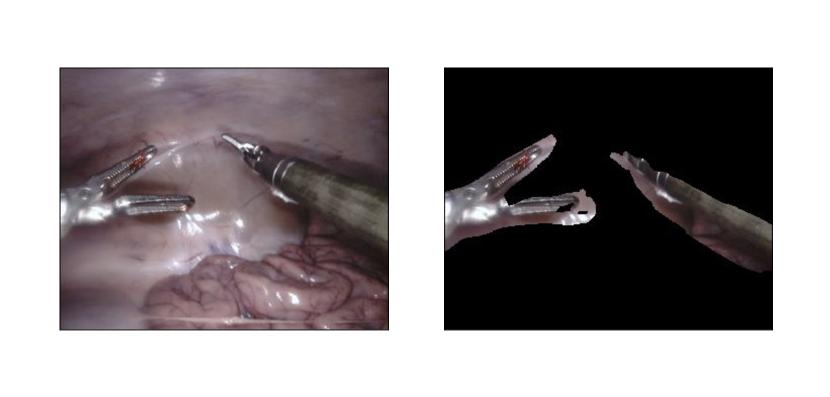

Refer to caption

Figure 1: Top row shows an example of synthetic annotation acquired using forward kinematics model that was used for training of our method. As it can be seen, it barely captures the actual tool due to errors. Two bottom rows show example segmentations delivered by our method on a random images from Endovis 2017 dataset that were not used for training.

Overall, three video sequences of different procedures were collected resulting in 666 thousand frames and annotations. As mentioned previously, annotations exhibit errors similar to example presented in Fig. 1. The process of the data creation is fully automatic and does not involve any manual annotation and, therefore, can be used to generate a dataset of potentially unlimited size (see Fig. 4).

Collected video sequences contain 3 different types of robotic surgical instruments: Large Needle Driver, Prograsp Forceps, Bipolar Forceps. An example image sample from the dataset is shown in Fig. 1. Although we were not able to collect video sequences featuring all instruments [2] because their CAD models are not available, we noticed that our approach successfully generalizes to previously unseen instruments.

We test our method on the EndoVis 2017 Robotic Instruments dataset [2]. There are 888 high resolution (1280×1024128010241280\times 1024) sequences with 225225225 frames each in the training dataset [2]. As mentioned previously, we did not use the training dataset of Endovis 2017 and, instead, trained our method on our data acquired with imprecise kinematics model. Each pixel is labeled as either tool or background. There are 101010 757575-frame sequences in the test dataset that features 7 different robotic surgical instruments [2]. Samples from the dataset and segmentations delivered by our algorithm are depicted in Fig. 1.

We used data from ten different test sequences of Endovis 2017 dataset to evaluate our trained instrument segmentation network. To assess generalizability of the developed algorithm, we also payed attention on how our method performed segmentation with instruments that were not represented in our collected dataset: our method successfully segmented previously unseen instrument (See bottom row of Fig. 1). Table I summarizes the quantitative results of the testing with intersection-over-union metric.